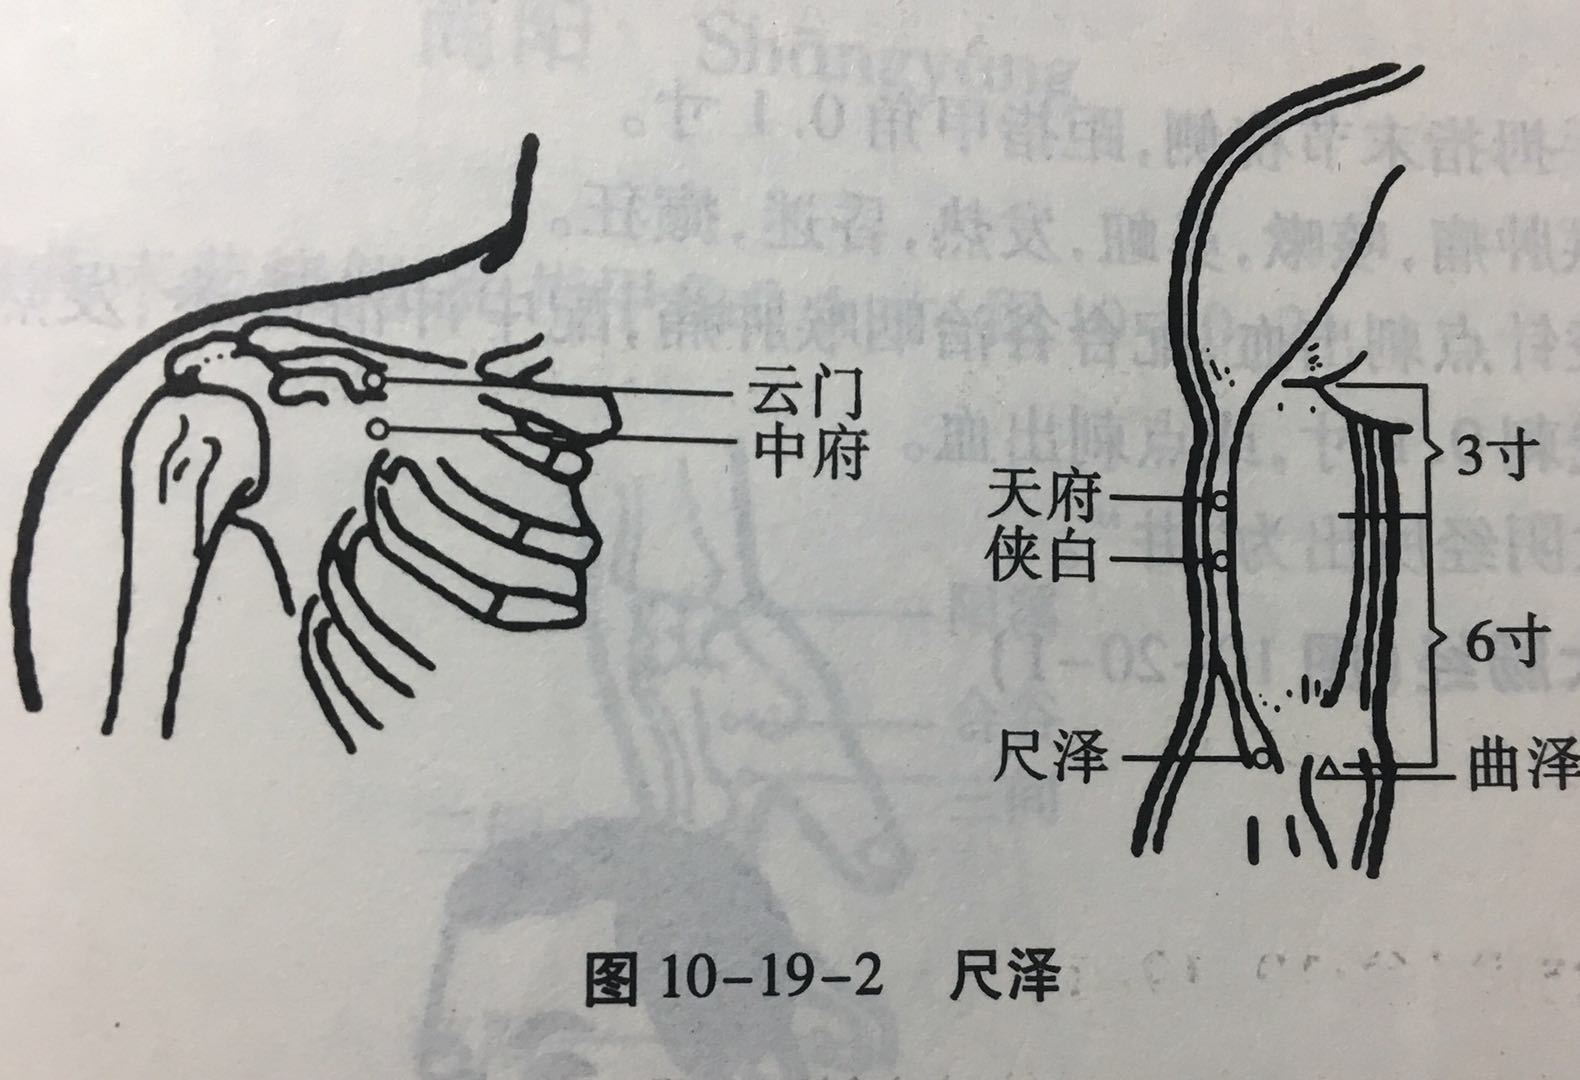

尺泽

【定位】 在肘横纹中,肱二头肌腱桡侧凹陷处(图 10-19-2)。

【主治】 咳嗽,气喘,咳血,潮热,胸部胀满,咽喉肿痛,小儿惊风,吐泻,肘臂挛痛。

【配伍】 配太渊、经渠治咳嗽、气喘,配孔最治咳血、潮热,配曲池治肘臂挛痛。

【刺灸法】 直刺 0.8 ~ 1.2 寸,或点刺出血。

【附注】 手太阴经所入为“合”。